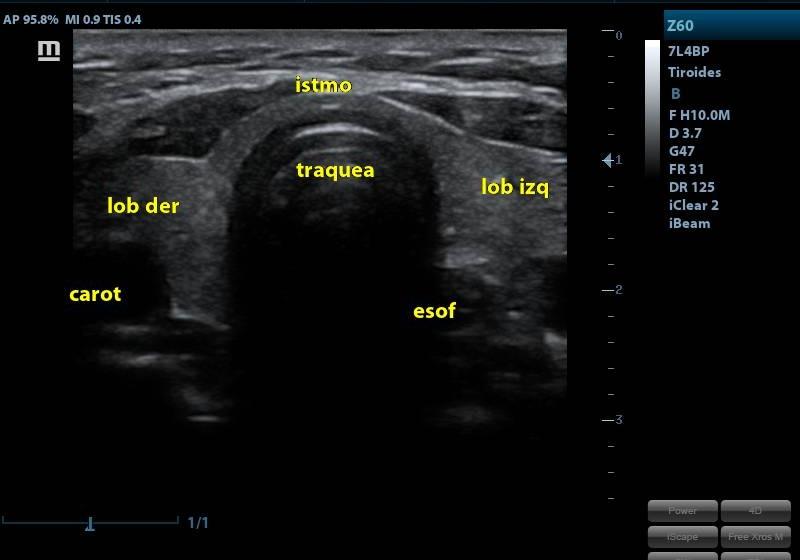

ECOGRAFIA DE TIROIDES

SERVICIOECOGRAFIA

PRESENTACIÓNECOGRAFIA

CONDICIÓNNO REQUIERE PREPARACION PREVIA

TIEMPO20 MINUTOS

TIPO RESULTADOSIMAGENES ECOGRAFICAS

ESPECIFICACIONESLa ecografía proporciona información morfológica general: presencia del órgano, posición, tamaño, forma, contornos, bordes y morfológica específica: ecogenicidad y ecoestructura de la glándula y de los nódulos cuando éstos están presentes